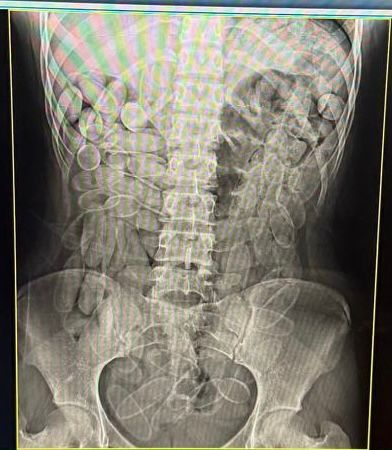

Imagem de raio-X revela cápsulas de droga ingeridas pelas jovens. Foto: Divulgação/Receita Federal As jovens foram encaminhadas à Santa Casa, onde exames de raio-X indicaram que ambas haviam ingerido 102 cápsulas cada uma. A droga apreendida totalizou aproximadamente dois quilos e duzentos gramas.

Dupla tentou entrar no país após engolir mais de 200 cápsulas de pasta base de cocaína. (Foto: Divulgação/Receita Federal)